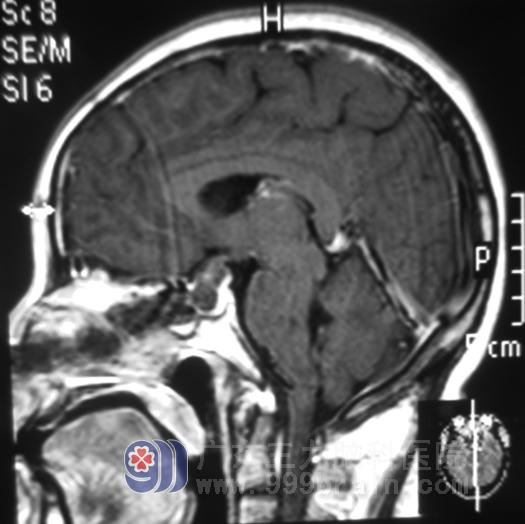

鲁明主任主刀,术前制定导航计划,术中再次导航定位肿瘤;术中见肿瘤伴有卒中,呈灰白色,质软,易吸出,包膜完整,镜下肿瘤全切除;鞍膈下陷,无脑脊液流出,术中未损伤视神经,修补颅底,经过顺利。术后未出现尿崩、离子紊乱、脑脊液漏等并发症,李姐的视力明显改善。术后病理:泌乳性垂体瘤。

手术后